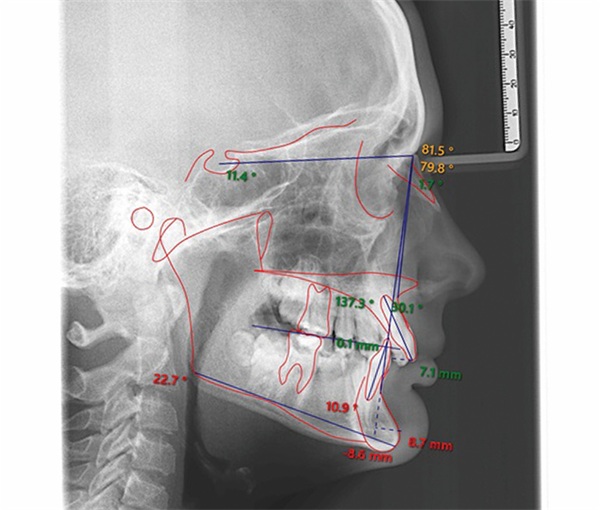

A 12-year-old male presented with severe Class II, deep bite, and significant crowding. The original poster was torn between two conflicting clinical pictures. Half the diagnostic findings pointed toward extraction: second molars impacted in the ramus, a blocked lower left canine, blocked maxillary canines, and a nearly full-step Class II relationship. The other half suggested non-extraction with vertical control to avoid deepening the bite further. The concern was that by the time crowding was resolved and the deep bite corrected, the incisors would be too flared for effective Class II correction without further proclination. The question posed to the forum was whether immediate upper first premolar and lower second premolar extractions were the best route forward (Figs. 1–11).

Before treatment planning could advance, multiple members flagged the need for better diagnostic records. The buccal photographs were not diagnostic, making it difficult to assess the true occlusal relationship. A severe transverse discrepancy was evident, along with possible soft tissue or skeletal asymmetry and potential maxillary cant. One clinician recommended obtaining a cone beam computed tomography scan to properly evaluate the asymmetry before finalizing any treatment plan. Another emphasized the importance of retraining staff on proper photo protocols to avoid similar issues in future cases. The original poster acknowledged the feedback and posted updated images.

The most frequently suggested treatment involved rapid palatal expansion followed by a Herbst appliance. Several clinicians viewed this as an ideal growth modification case given the patient’s age, low mandibular plane angle, and Class II presentation. Expansion would address the transverse deficiency first, with Herbst therapy used to advance the mandible and distalize the maxillary segment while creating space for the blocked canines. Because the lower incisors were upright and the patient exhibited a low-angle pattern, contributors felt the lower arch could tolerate some proclination. Opinions varied on lower appliance design, with some recommending premolar crowns and lingual arch support to help manage canine alignment while minimizing unwanted incisor effects.

One contributor emphasized that this was not a surgical case and argued that fixed functional therapy offered a predictable approach through tooth movement. They viewed a Herbst as the most predictable way to distalize upper molars while acknowledging that the panoramic radiograph showed evidence of posterior mandibular crowding. Depending on the severity of that crowding, either upper first premolar and lower second premolar extractions or Herbst therapy could yield good results.